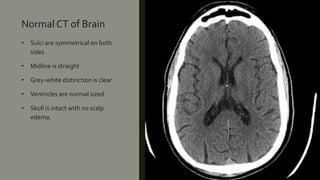

Normal CT of Brain

• Sulci are symmetrical on both

sides

• Midline is straight

• Grey-white distinction is clear

• Ventricles are normal sized

• Skull is intact with no scalp

edema.